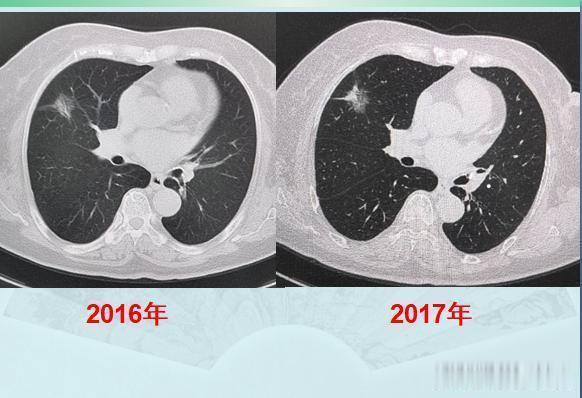

今天遇到的两位肺癌病人,让人很是感慨:癌症病人的运气,太重要!第一位,乳腺癌手术后2年又查出肺癌,拖了两年才手术,很成功!这是一位71岁的老太太,乳腺癌手术后定期体检,又发现右肺磨玻璃结节灶,大小2.0厘米:

很多人的运气不够好,一辈子会得两次癌症,甚至有极少数人会多次患癌。这位老太太会不会是肺癌呢?病人拒绝了进一步检查,选择随访观察,走一步看一步吧,就这样随访了两年,每年做一次肺CT:

文章插图

CT显示,这个混合磨玻璃结节边界清晰,以一种很缓慢的速度在增长,白色的实性成分在增加,并且开始出现胸膜牵拉,这提示典型的肺腺癌征象了。在前面的《豪大夫讲肺结节》系列文章种,又一个肺腺癌的知识点我们反复提起过:边界清晰的混合磨玻璃结节,伴有胸膜牵拉,诊断肺腺癌准确率极高!CT图片就可以诊断肺癌了,甚至不需要穿刺病理。并且我们也提过,伴有胸膜牵拉的肺腺癌,癌细胞容易沿着胸膜的脉管系统(主要是淋巴)发生转移,很多人会因此失去手术机会,有些肿瘤甚至还不到2厘米。这个病灶不能拖了!后来经过商议,老人去胸外科做了胸腔镜微创手术切除,病理是浸润性肺腺癌(贴壁生长为主,伴有腺泡和乳头状生长,属于中高分化),胸膜尚未受累,清扫了8枚淋巴结也未发现癌细胞转移!今年已经两年了,今天复查没有复发,恢复很好!